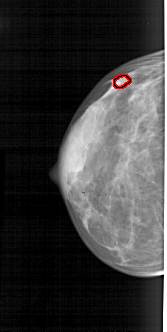

A_1841_1.LEFT_MLO

LEFT_MLO LINES 5041 PIXELS_PER_LINE 2626 BITS_PER_PIXEL 12 RESOLUTION 43.5 OVERLAY

FILE: A_1841_1.LEFT_MLO.OVERLAY

TOTAL_ABNORMALITIES 1

ABNORMALITY 1

LESION_TYPE CALCIFICATION TYPE PLEOMORPHIC DISTRIBUTION CLUSTERED

ASSESSMENT 4

SUBTLETY 1

PATHOLOGY BENIGN

TOTAL_OUTLINES 1

BOUNDARY